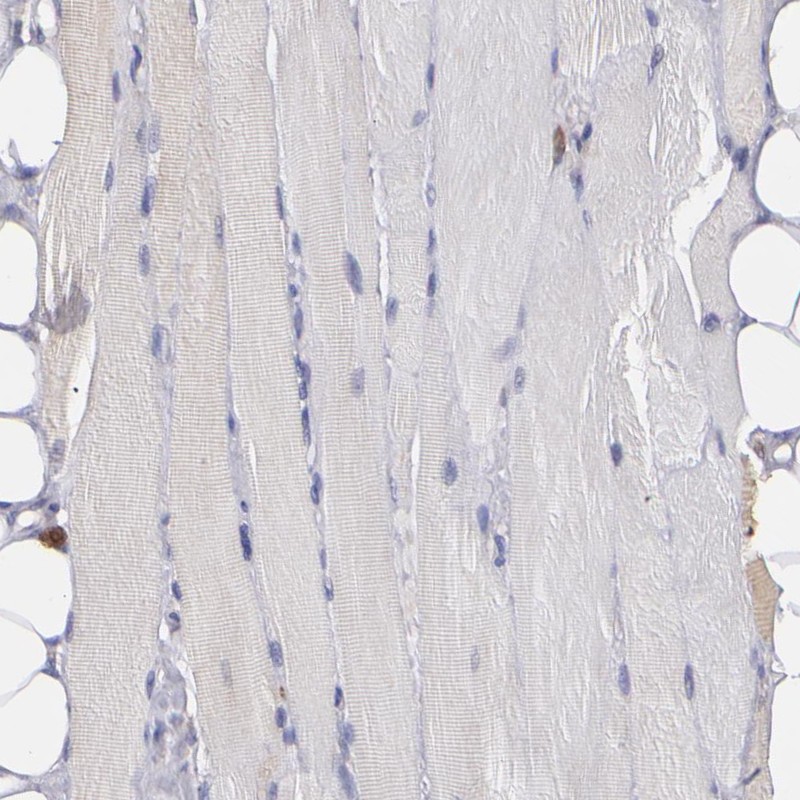

Immunohistochemistry analysis in human skin and skeletal muscle tissues using Anti-PTGS1 antibody. Corresponding PTGS1 RNA-seq data are presented for the same tissues.